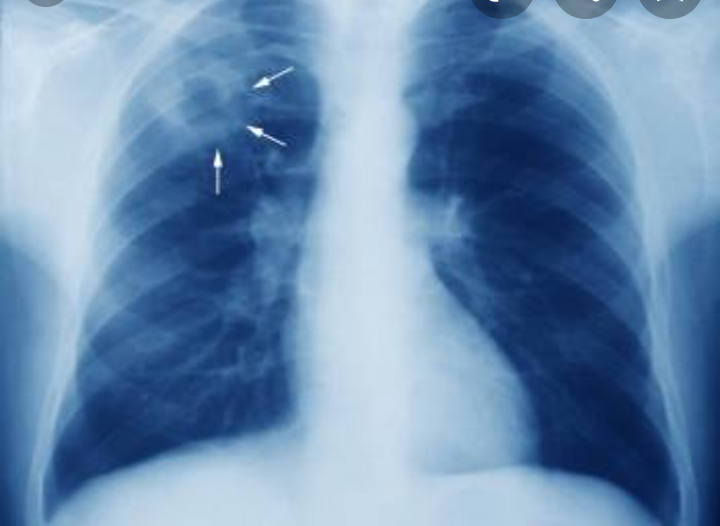

Parmi les politiques qui ont porté leurs fruits, citons le développement de l'utilisation de technologies numériques telles que le diagnostic assisté par ordinateur pour les radiographies pulmonaires - particulièrement utile dans les pays qui ne disposent pas d'un nombre suffisant de radiographes qualifiés - ainsi que la fourniture de conseils et d'un soutien à distance et la mise en place de services de prévention et de traitement de la tuberculose à domicile.